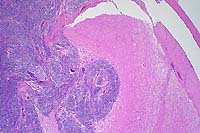

- Case 6-3. Liver. Large areas of liver parenchyma

are expanded, separated, and replaced by a pleocellular infiltrate.

There is preservation of the major vessels and some bile ducts,

but in the center of this mass there is effacement of hepatic

plates.

- Case 6-3. Liver. Infiltrating cells include abundant

eosinophils with lesser numbers of large pleomorphic round cells

admixed with fewer small lymphocytes. Occasional large atypical

cells are associated with numerous 2-3u small basophilic bodies

(lymphoglandular bodies?). A residual bile duct is at the lower

left and strip of brown pigment bearing hepatocytes are at the

upper right.